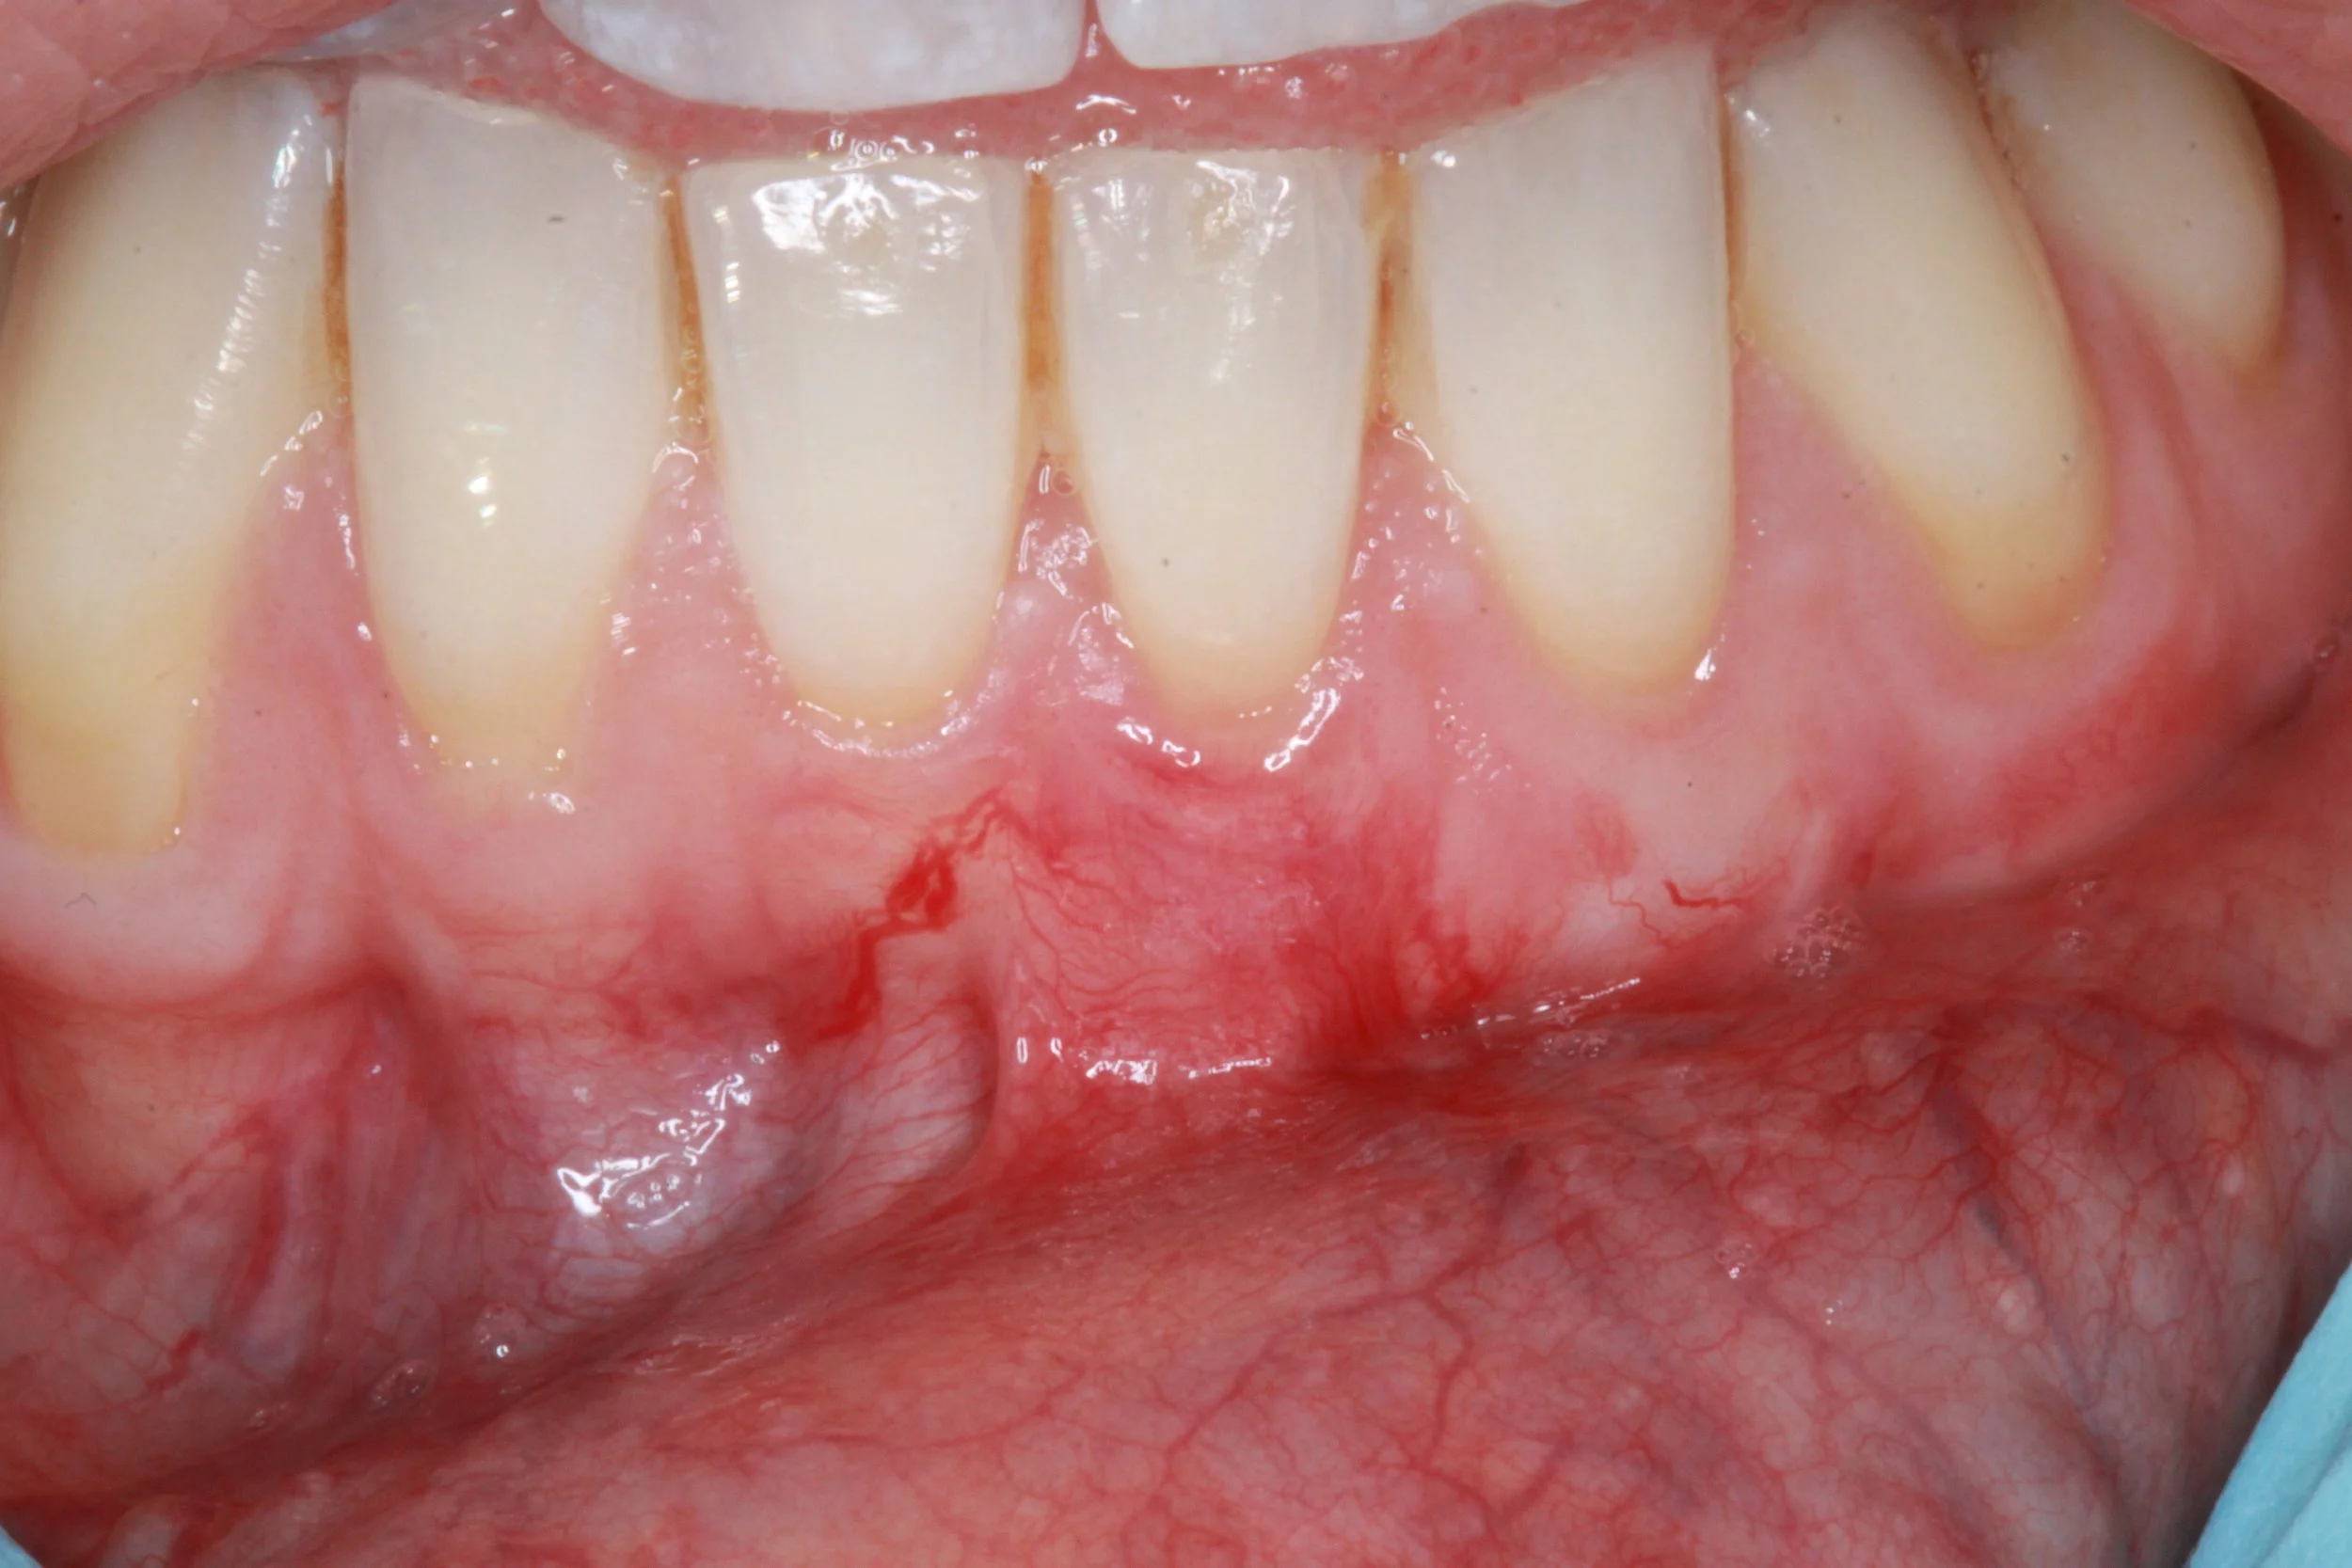

Gum recession occurs when the gum line pulls away from the teeth, exposing the roots and leading to sensitivity, a “long-tooth” appearance, and increased risk of decay. it can develop from factors such as periodontal disease, aggressive brushing, genetics, or teeth grinding.

Periodontists specialise in diagnosing the underlying cause of recession and restoring lost tissue with advanced techniques such as minimally invasive grafting. Early assessment and personalised treatment can protect your teeth, improve comfort, and enhance your smile’s aesthetics.